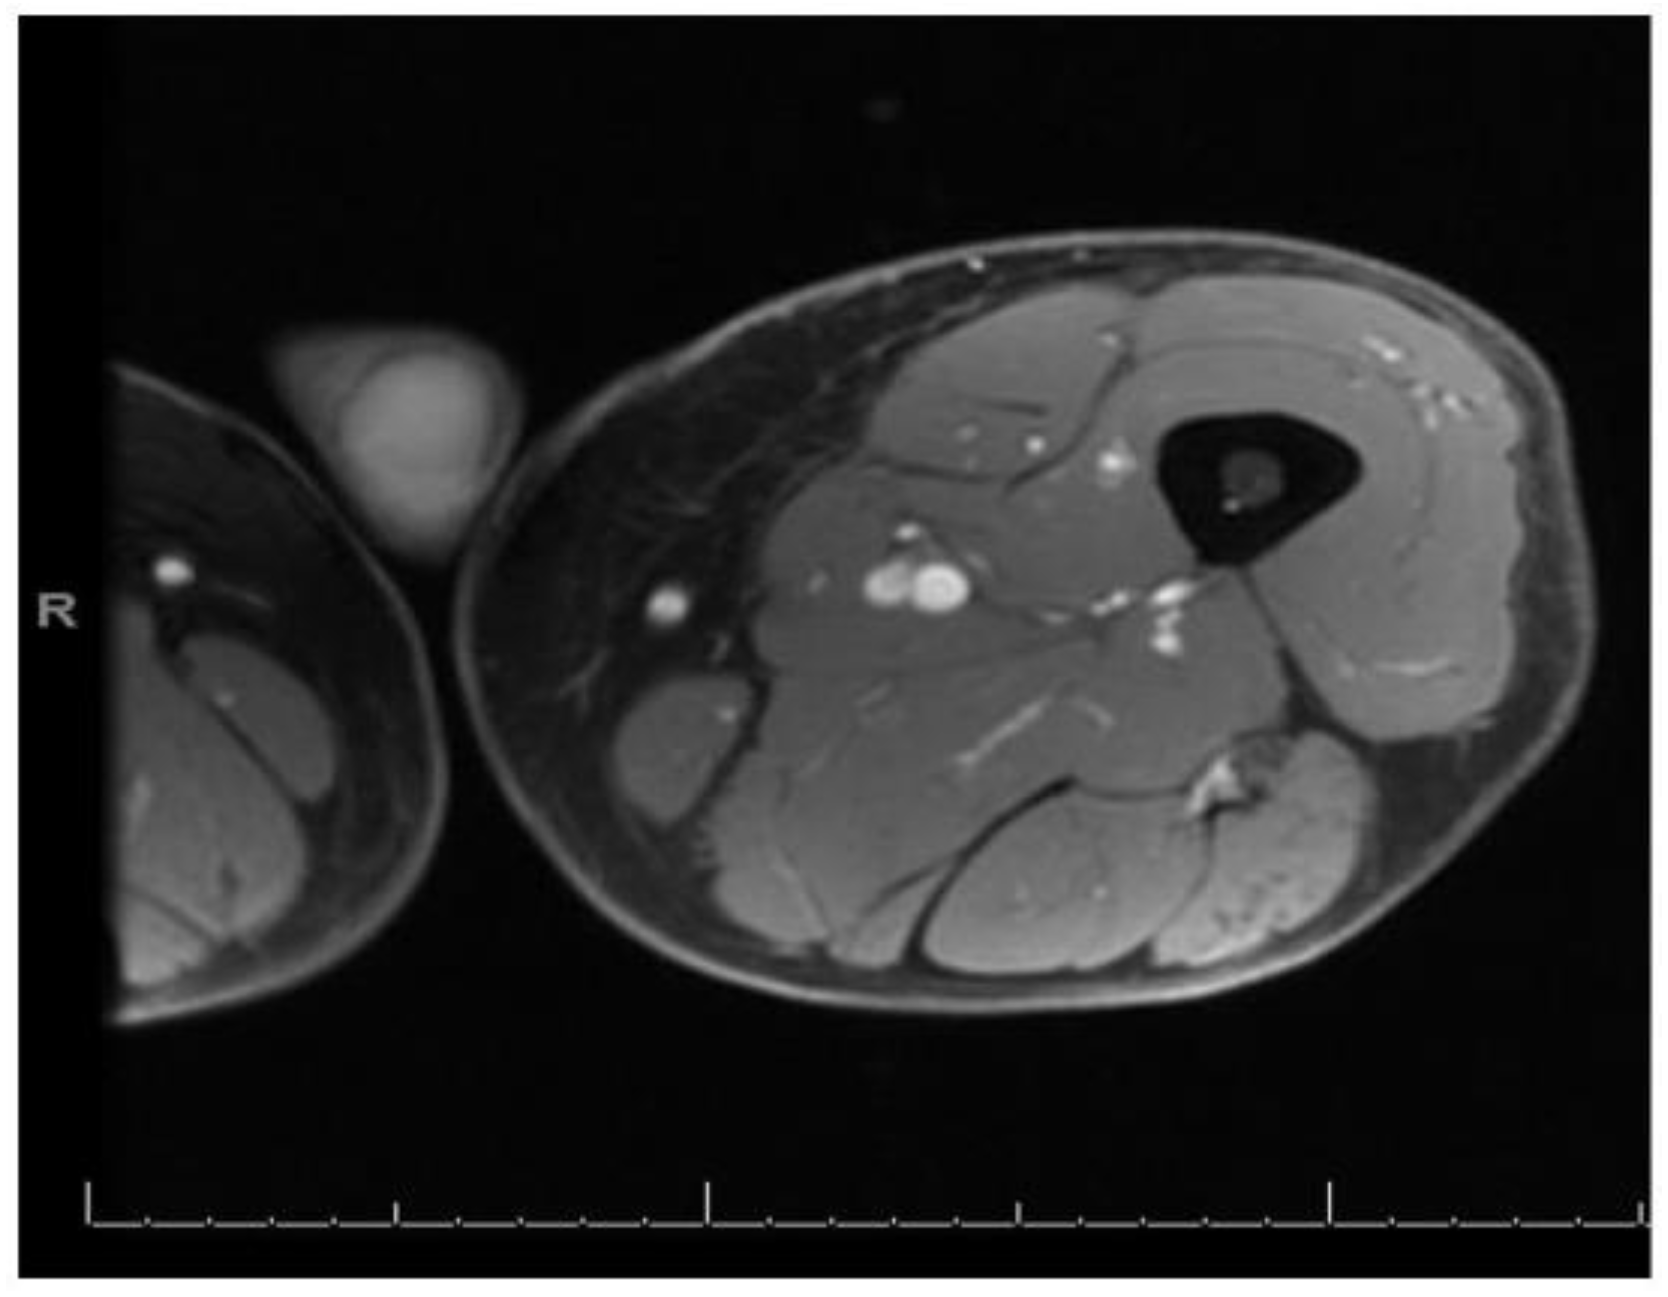

After almost about 10 days of antibiotics, the patient started to have a gradual improvement in pain and muscle weakness. He was discharged in a stable condition at day 14 to continue 2 more weeks of oral antibiotics and with recommendation for outpatient follow up. After 2 months of initial presentation, patient was seen at his family physician’s office at which time he had complete resolution of the weakness and diffuse muscle pain. However, he complained of one tender lump at the distal and medial aspect of left thigh and there was no sign of infection. Outpatient MRI of the left thigh showed resolution of previous foci of abnormal signal within the thigh musculature (Figure 2); however, a new 2.5 cm peripherally enhancing lesion within the vastus medialis muscle was seen, with possible differentials of hematoma, abscess, and myonecrosis. An ultrasound guided aspiration of the mass was attempted; the ultrasound, however, did not show a loculated fluid collection, and core biopsies were obtained from the distal medial left thigh from a location with altered architecture as noted in MRI. The tissue specimen was reported as skeletal muscle with endomysial and perimysial chronic inflammation and atrophy. Microscopic evaluation showed no polymorphonuclear leukocytes and no growth on cultures. An immune-histochemical stain was positive for leukocyte common antigen (LCA) confirming a marked lymphocytic component, with plans for further special histochemical studies.

Figure 2. MRI of left thigh with resolution of diffuse edema and previous foci of multiple nodular and ring enhancing lesions.